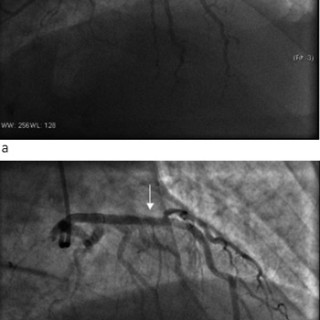

HACEK er et akronym som refererer til en gruppe taksonomisk ulike bakterier med en rekke fellestrekk. Det står for Haemophilus parainfluenzae, Aggregatibacter (A aphrophilus, A actinomycetemcomitans), Cardiobacterium spp., Eikenella corrodens og Kingella kingae (1, 2). Alle disse har en tendens til å forårsake endokarditt, men de var tidligere lite kjent fordi de er vanskelige å få til å vokse. HACEK-endokarditt havnet derfor i gruppen kulturnegative endokarditter. Fremdeles forblir mange av disse endokardittene kulturnegative. Bakteriene er små, gramnegative staver tilhørende den...